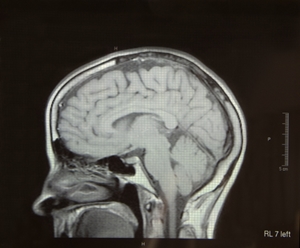

The MRI machines were sent to combat zones to provide doctors with the ability to respond more quickly to the traumatic brain injuries that affect troops due to roadside bombs and other blasts, the news source noted. However, a senior medical officer for the U.S. Central Command said it was unclear whether the machines were helping doctors treat these injuries in combat.

"The device itself doesn't necessarily help you treat that patient, it just helps you understand the nature of the injury in a little bit more meaningful way," Air Force Col. Mark Mavity, a Central Command surgeon, told the news outlet. "[It] was deemed not worth the cost and investment to keep those devices in theater."